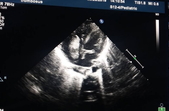

«Хлопчик із Житомирської області, що народився місяць тому на 29 тижні вагітності з вагою 1400 г, сьогодні був доставлений в Інститут серця МОЗ України швидкою з діагнозом субтотальний тромбоз правого передсердя і флотируючими тромбами лівого передсердя. Напередодні консиліум лікарів разом з директорм Інституту серця Борисом Тодуровим прийняли рішення щодо можливості проведення термінової операції», - поінформували в Інституті серця.

Година знадобилася лікарям на діагностику і підготовку дитини на екстрену операцію. Операція з видалення тромбів проводилася зі штучним кровообігом, а під час основного етапу - на тлі глибокої гіпотермії та повної зупинки кровообігу.